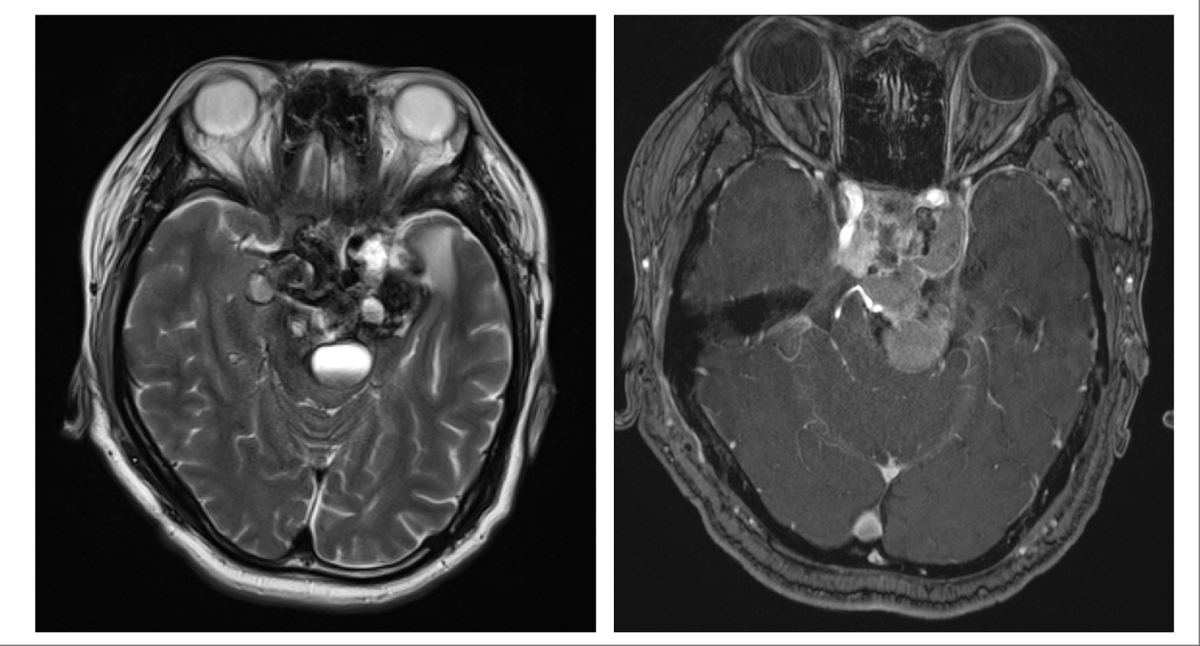

腦幹腫瘤。(受訪者供圖)

腦腫瘤又名「顱內腫瘤」,由頭顱內的細胞不正常生長引起,可分為「良性」或「惡性」。值得留意的是,與其他器官相比,腦瘤的整體發病率相對較低,且約85%為良性腫瘤,預後相對樂觀。良性腫瘤一般生長較慢、具有完整包膜而具並不會入侵組織,以腦膜瘤、腦下垂體瘤最為常見;惡性腫瘤一般生長迅速,沒有完整外膜和明顯邊界,會侵蝕到組織或轉移到其他器官。

其中,惡性腦瘤亦可分為轉移性與原發性兩大類,轉移性腦腫瘤(metastasis)由發生在身體其他部位(如鼻咽癌、乳癌和肺癌等)的原發癌轉移或擴散至腦部;原發性惡性腦腫瘤,是指腫瘤在原本的位置不斷生長和增大,雖然在所有惡性腫瘤中只約佔1-2%,但情況較不樂觀,死亡率亦高,其中接近80%為膠質瘤(glioma),源自腦部星形細胞等膠質細胞的變異。其中,第四級的「膠質母細胞瘤(Glioblastoma, GBM)」惡性度最高、生長迅速且復發率高,常見於40歲以上人士,患者存活期通常僅有9至15個月。腫瘤的發生位置、患者基因背景及家族病史均可能影響發病風險。